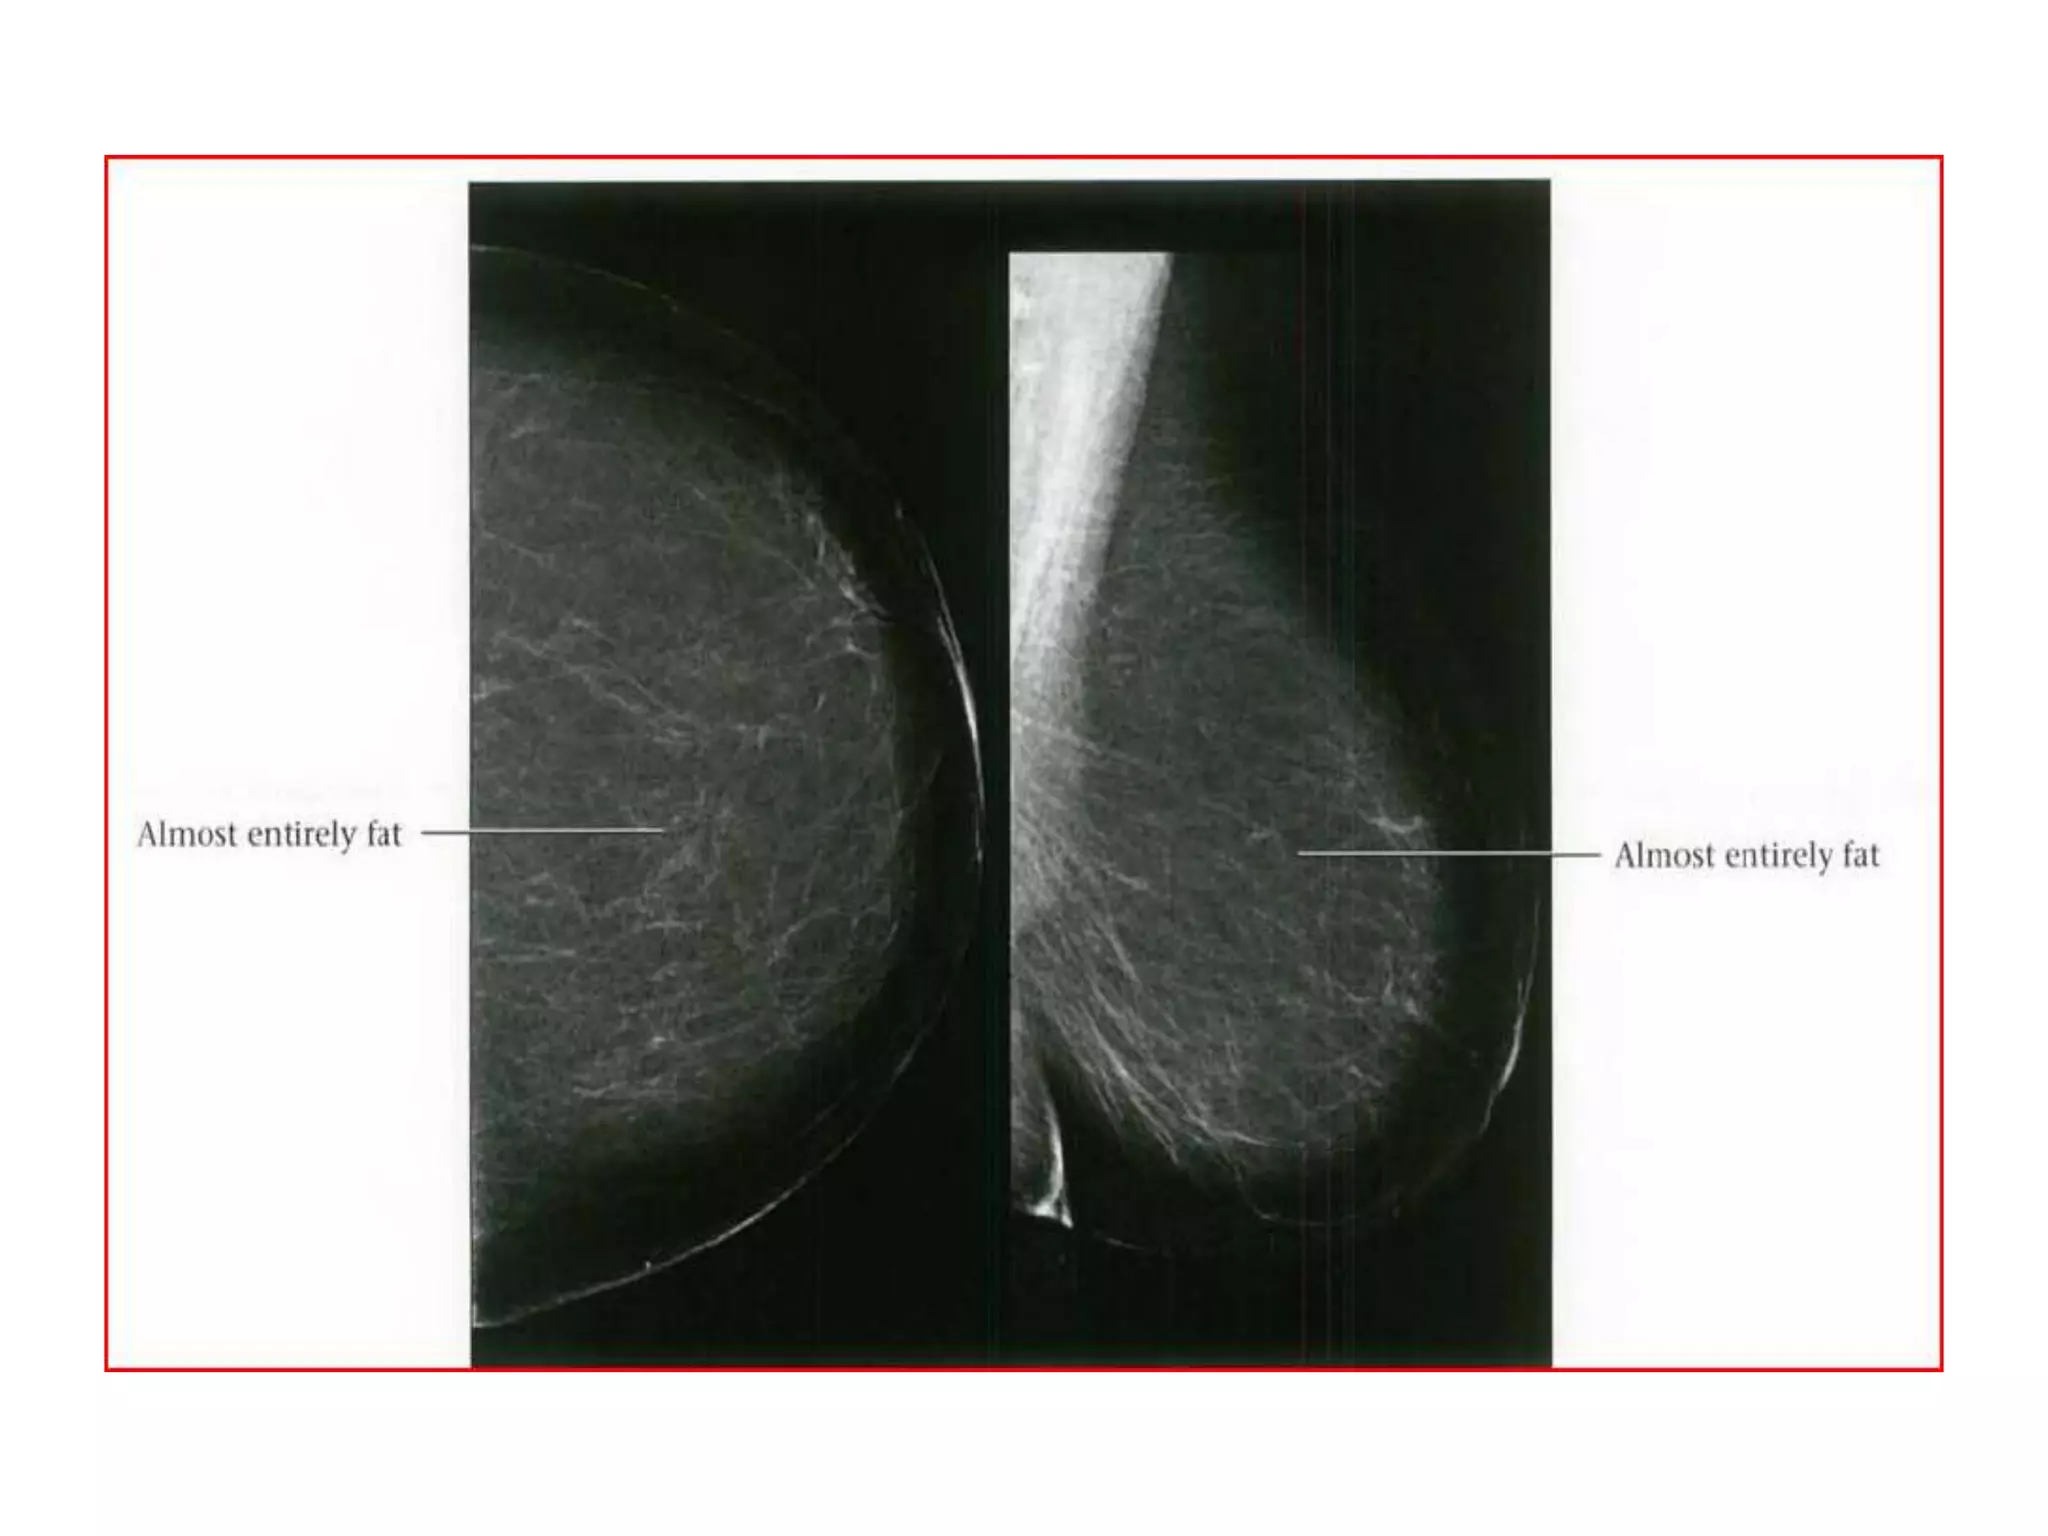

BI-RADS BREAST COMPOSITION

• The American College of Radiology Breast

Imaging and Reporting Database System (BIRADS)divides breast composition into four

categories:

• 1) almost entirely fat,

• 2) scattered fibroglandular densities

(approximately 25-50% glandular),

• 3) heterogeneously dense (51-75% glandular),

• 4) extremely dense (greater than 75% glandular).